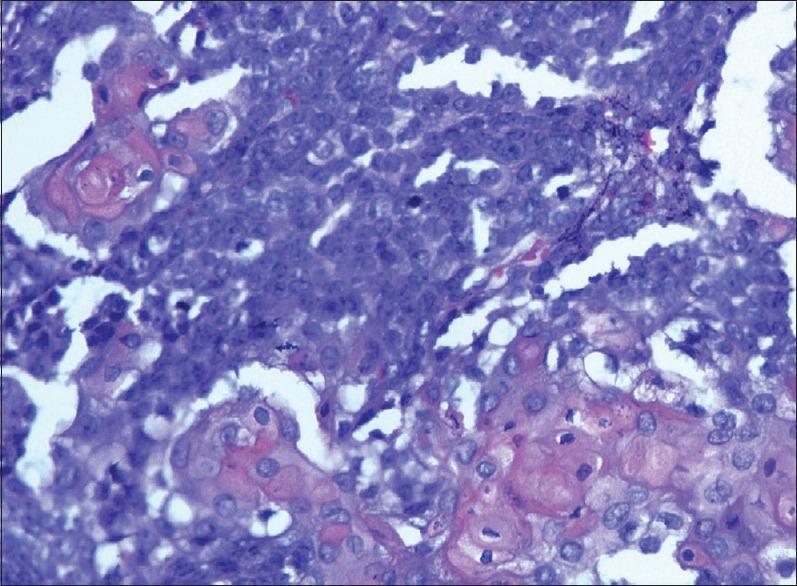

Odontogenic ghost cell carcinoma (OGCC) is an exceptionally rare malignant odontogenic epithelial tumor. It is characterized by ameloblastic-like islands of epithelial cells with aberrant keratinization in the form of ghost cells with varying amounts of dysplastic dentin. Malignant histological characteristics include infiltration, cellular pleomorphism, numerous mitosis and necrosis. Its biological behavior varies from slow-growing locally invasive lesions to rapidly growing highly aggressive tumors. OGCC metastasizing to distant sites is extremely rare. Only three cases of metastasis have been reported in literature. We are reporting the case of a 54-year-old male patient who presented with tender swelling in the malar region. Histopathological examination revealed OGCC and he received postoperative radiotherapy. Two years later, he presented with a lung mass. Biopsy from the lung lesion showed the same morphology as that of maxillary tumor with scattered ghost cells. This case points to the aggressive behavior of OGCC and its metastatic potential. It also highlights the need for long-term follow-up of these patients.

牙源性影细胞癌(OGCC)是一种极为罕见的恶性牙源性上皮肿瘤。其特征为上皮细胞呈成釉细胞样岛状排列,伴有异常角化,形成影细胞,并伴有不同程度的发育异常牙本质。恶性组织学特征包括浸润、细胞多形性、大量有丝分裂和坏死。其生物学行为从生长缓慢的局部浸润性病变到生长迅速的高度侵袭性肿瘤不等。OGCC转移至远处部位极为罕见。文献中仅报道了3例转移病例。我们报告一例54岁男性患者,其颧部出现压痛性肿胀。组织病理学检查显示为OGCC,患者接受了术后放疗。两年后,他出现肺部肿块。肺部病变活检显示与上颌肿瘤形态相同,可见散在的影细胞。该病例表明OGCC具有侵袭性生物学行为及其转移潜能。它还强调了对这些患者进行长期随访的必要性。